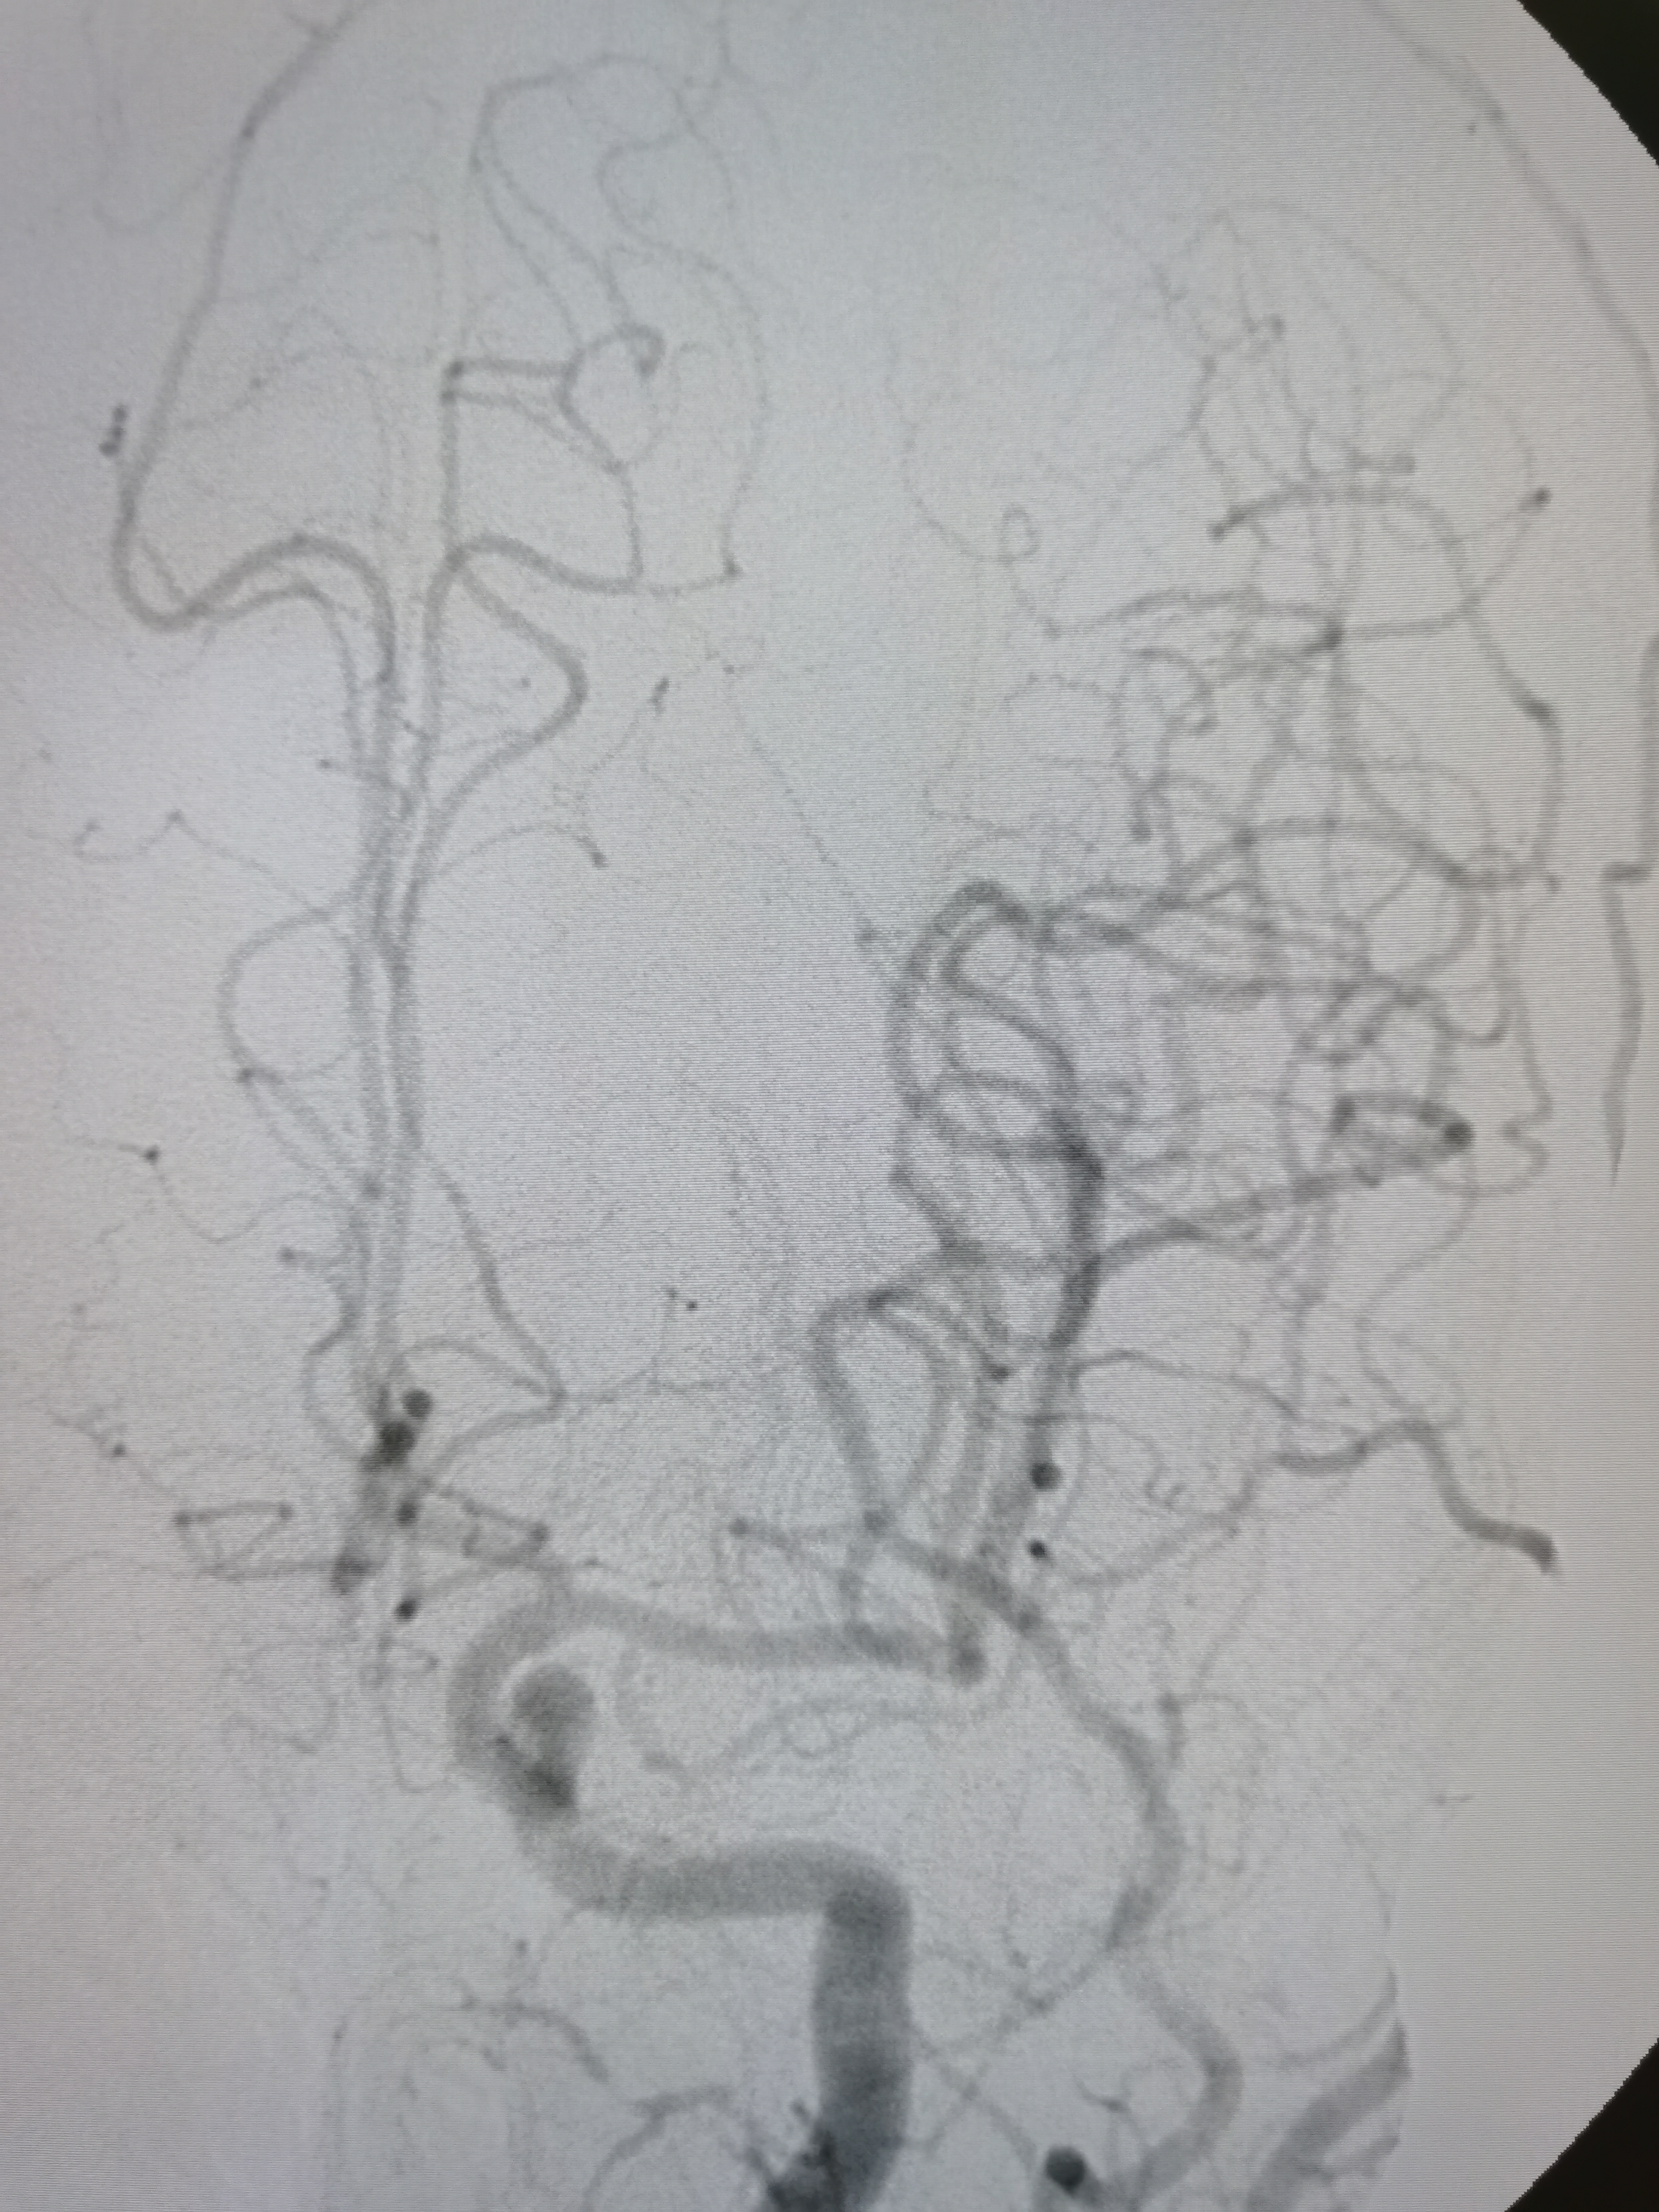

右侧颈内动脉起始部重度狭窄。

颅内段显影可。

右侧孤立大脑中动脉,M1轻度狭窄。